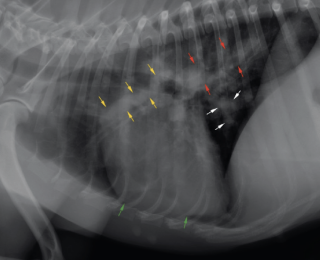

Thoracic radiographs revealed enlargement of the pulmonary arteries, mild to moderate right ventricular enlargement and a moderate diffuse, unstructured interstitial pattern with patchy alveolar areas within the right cranial and middle lung lobes (see Figures 1 and 2). Echocardiography revealed right atrial enlargement with bulging of the interatrial septum to the left, mild subjective enlargement of the right ventricle and mild to moderate central pulmonic regurgitation with a mildly elevated velocity (2.8m/s; reference value <2.2m/s). The pulmonary artery was mildly enlarged and contained multiple mobile, tortuous linear hyperechoic structures, likely to reflect the presence of adult worms (see Figure 3). The laboratory test results in combination with the imaging findings were consistent with a diagnosis of canine dirofilariasis.